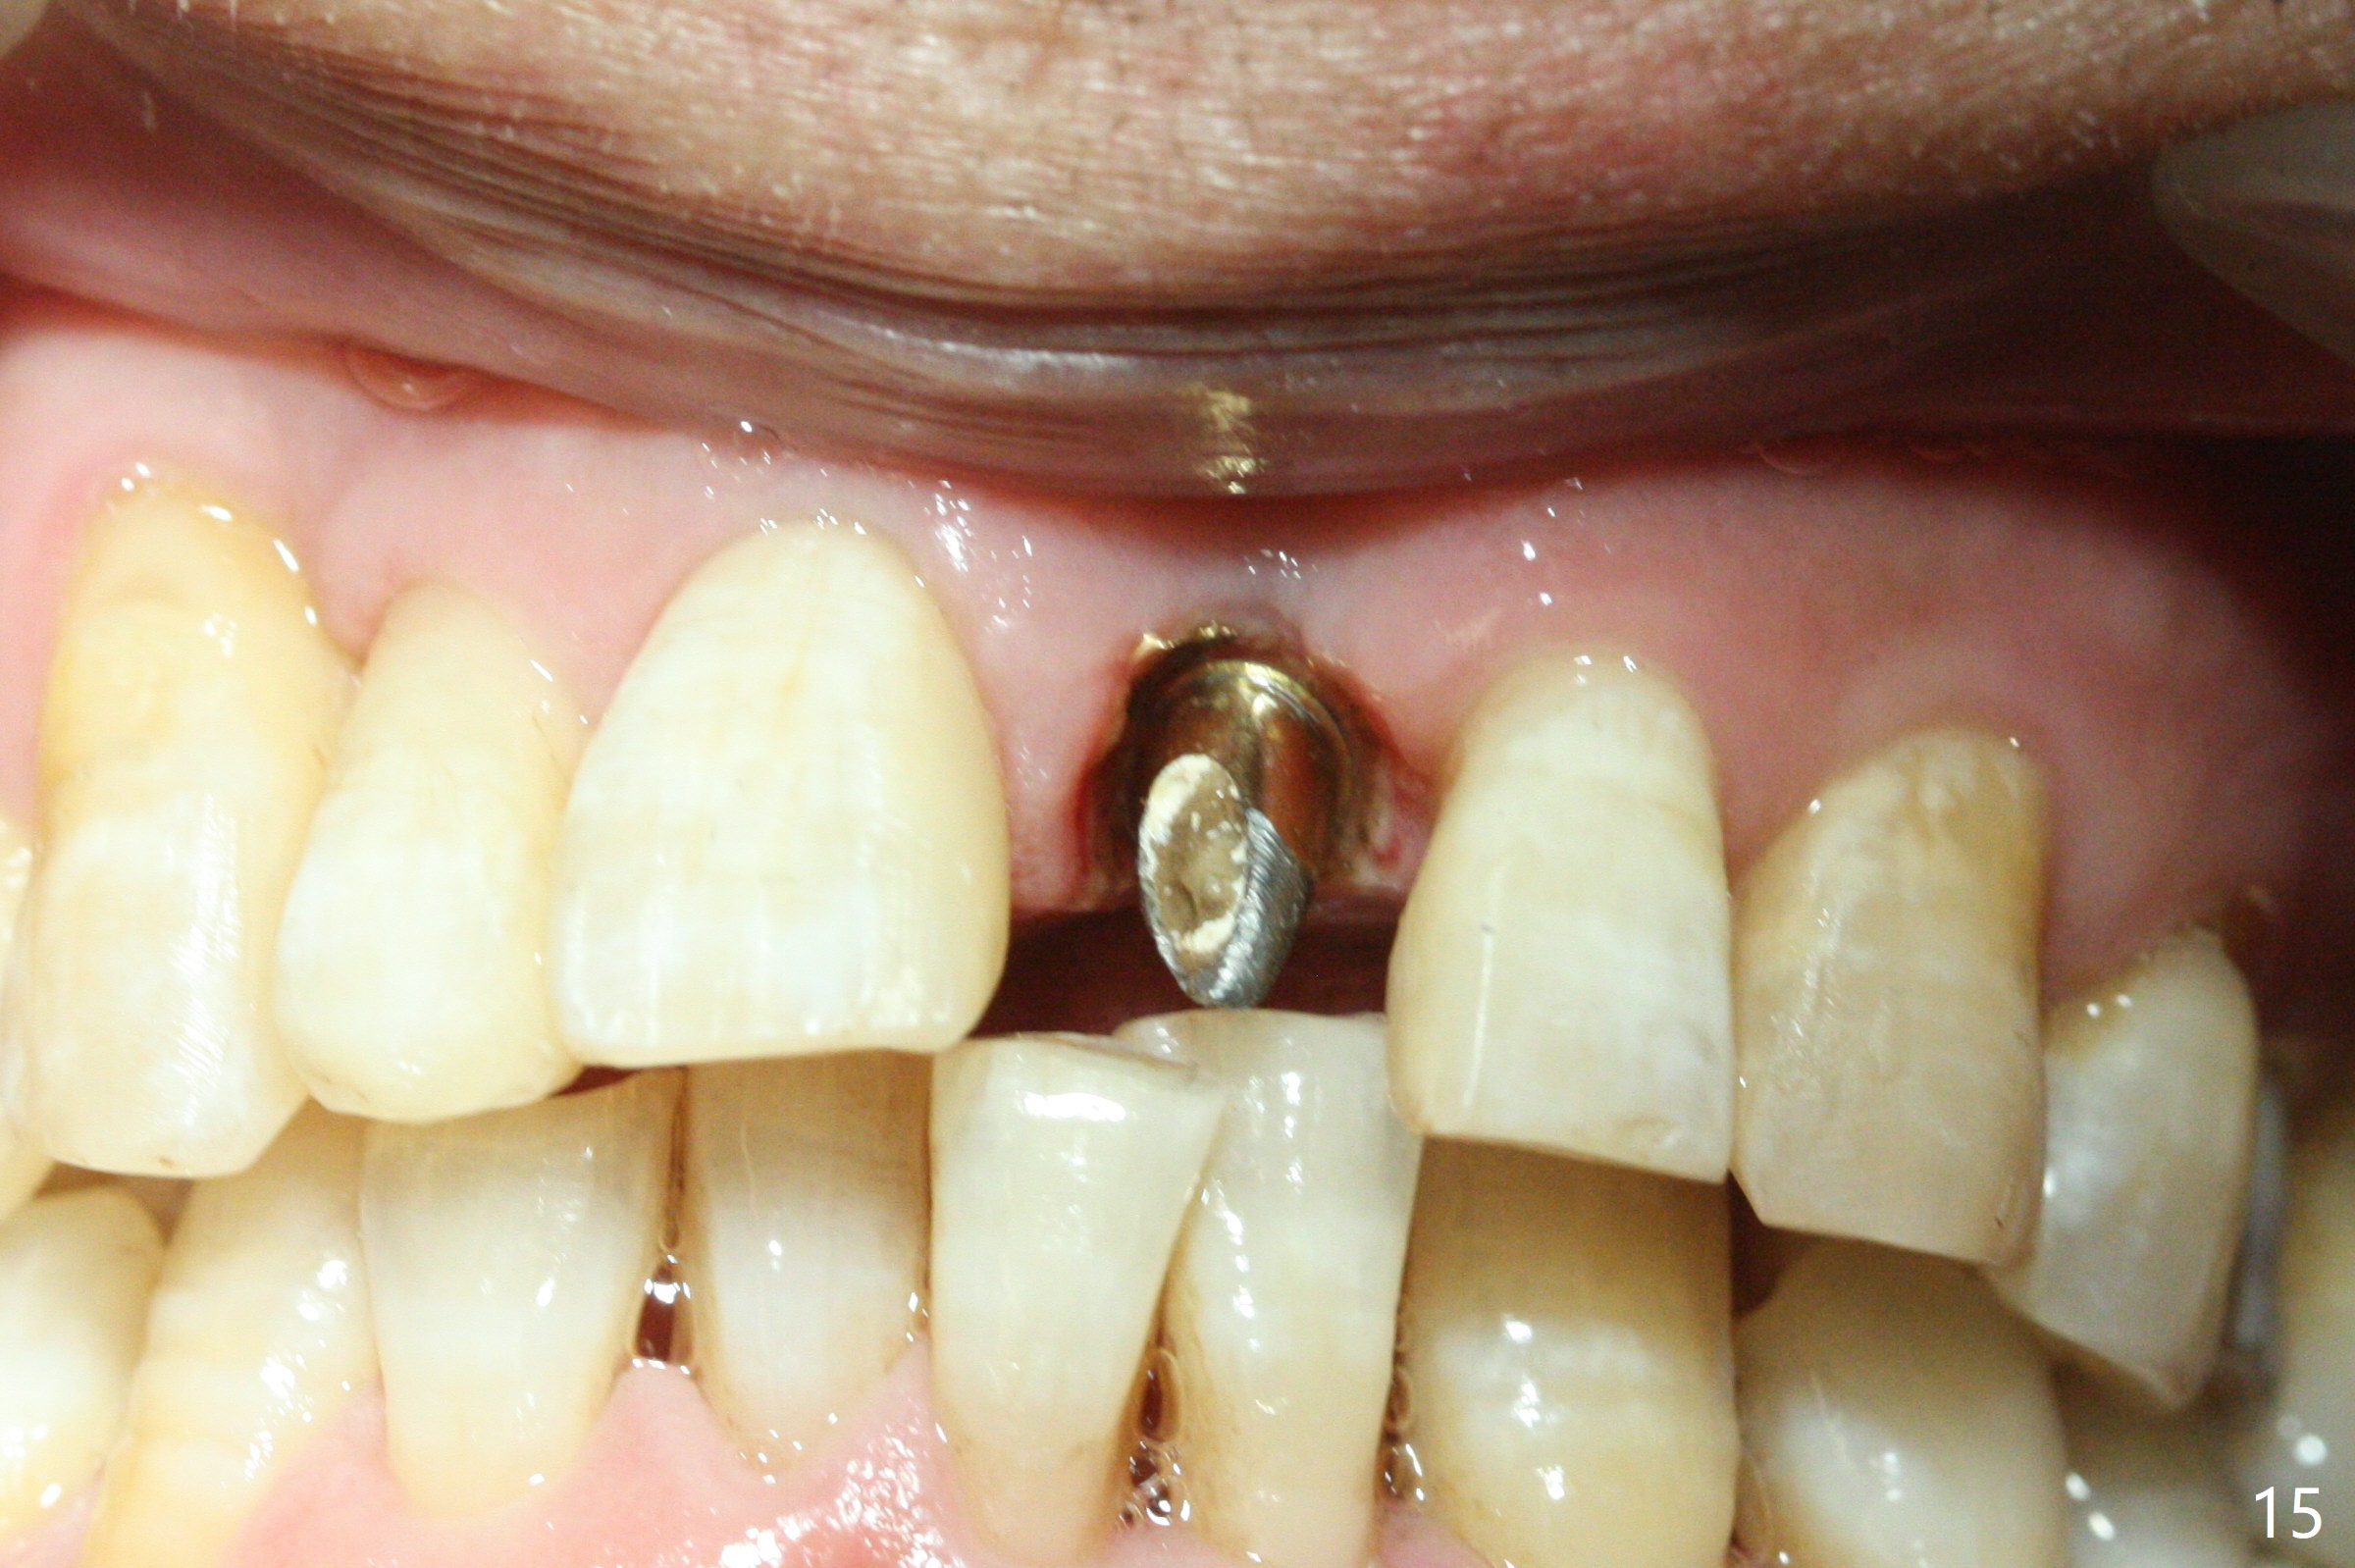

Nearly 7 months postop, the immediate provisional at UL1 is removed; with the mesial reduction of UL2 from 7 to 6 mm (Fig.1), an angled abutment is to be changed (4.5x15 degree, 2 mm cuff). A new provisional (Fig.2,3) co-incides with the facial midline. Brackets will be placed between UR4 to UL3 except UL2 (symptomatic once with chronic periodontitis) with initial proximal reduction between UR1-4 in preparation to correct cross bite of UR2. Twelve days later, the patient returns for UR5-UL3 bracketing after UR1-4 initial proximal reduction with 14 niti wire (Fig.4-6). UR1 moves mesial 20 days post open coil spring (Fig.7 arrow), while UL1 debracketes after permanent re-cementation of the temporary crown last visit (*, no re-bracketing, since it appears not essential). Before placement of 20 ss wire, diastemata are created by proximal reduction (Fig.8 *). In fact UR1 moves mesial, while UR3 does not move distal with the open coil. With placement of UR6 (implant) molar band, UR3 is distalized effectively. With sling shot, UR2 is almost labialized in one appointment (Fig.9). After consolidation of the diastemata between UR1-6 with power chains following UR2 cross bite correction (Fig.10), the restoration space for UL1 seems to be too large (Fig.11). Next visit, check the midlines, take 1-2 PAs for #7-9 and determine whether a straight abutment should be changed back and whether composite should be placed UR1 mesial to reduce the space. One week later, composite is added to the mesial surface of the tooth #8 to increase its width, while the provisional at #9 is relined to improve the interdental papilla (Fig.12). Minimal bone loss at UR2 is observed 8 months post banding (Fig.13), while the socket at UL1 seems to have healed except the most coronal 1 year 3 months postop (Fig.14 *). The margin of the abutment should be uneven, more coronal proximal than buccopalatal (Fig.15). The final crown has an open margin, partially due to less ideal trajectory (Fig.16 (black line: ideal trajectory, nearly 1 year 4 months postop)). Guided surgery could solve the problem. Sticky bone may restore the buccal plate defect. Die shows that the implant is palatally placed (Fig.17). CT will be taken to determine whether the implant perforates the palatal plate.